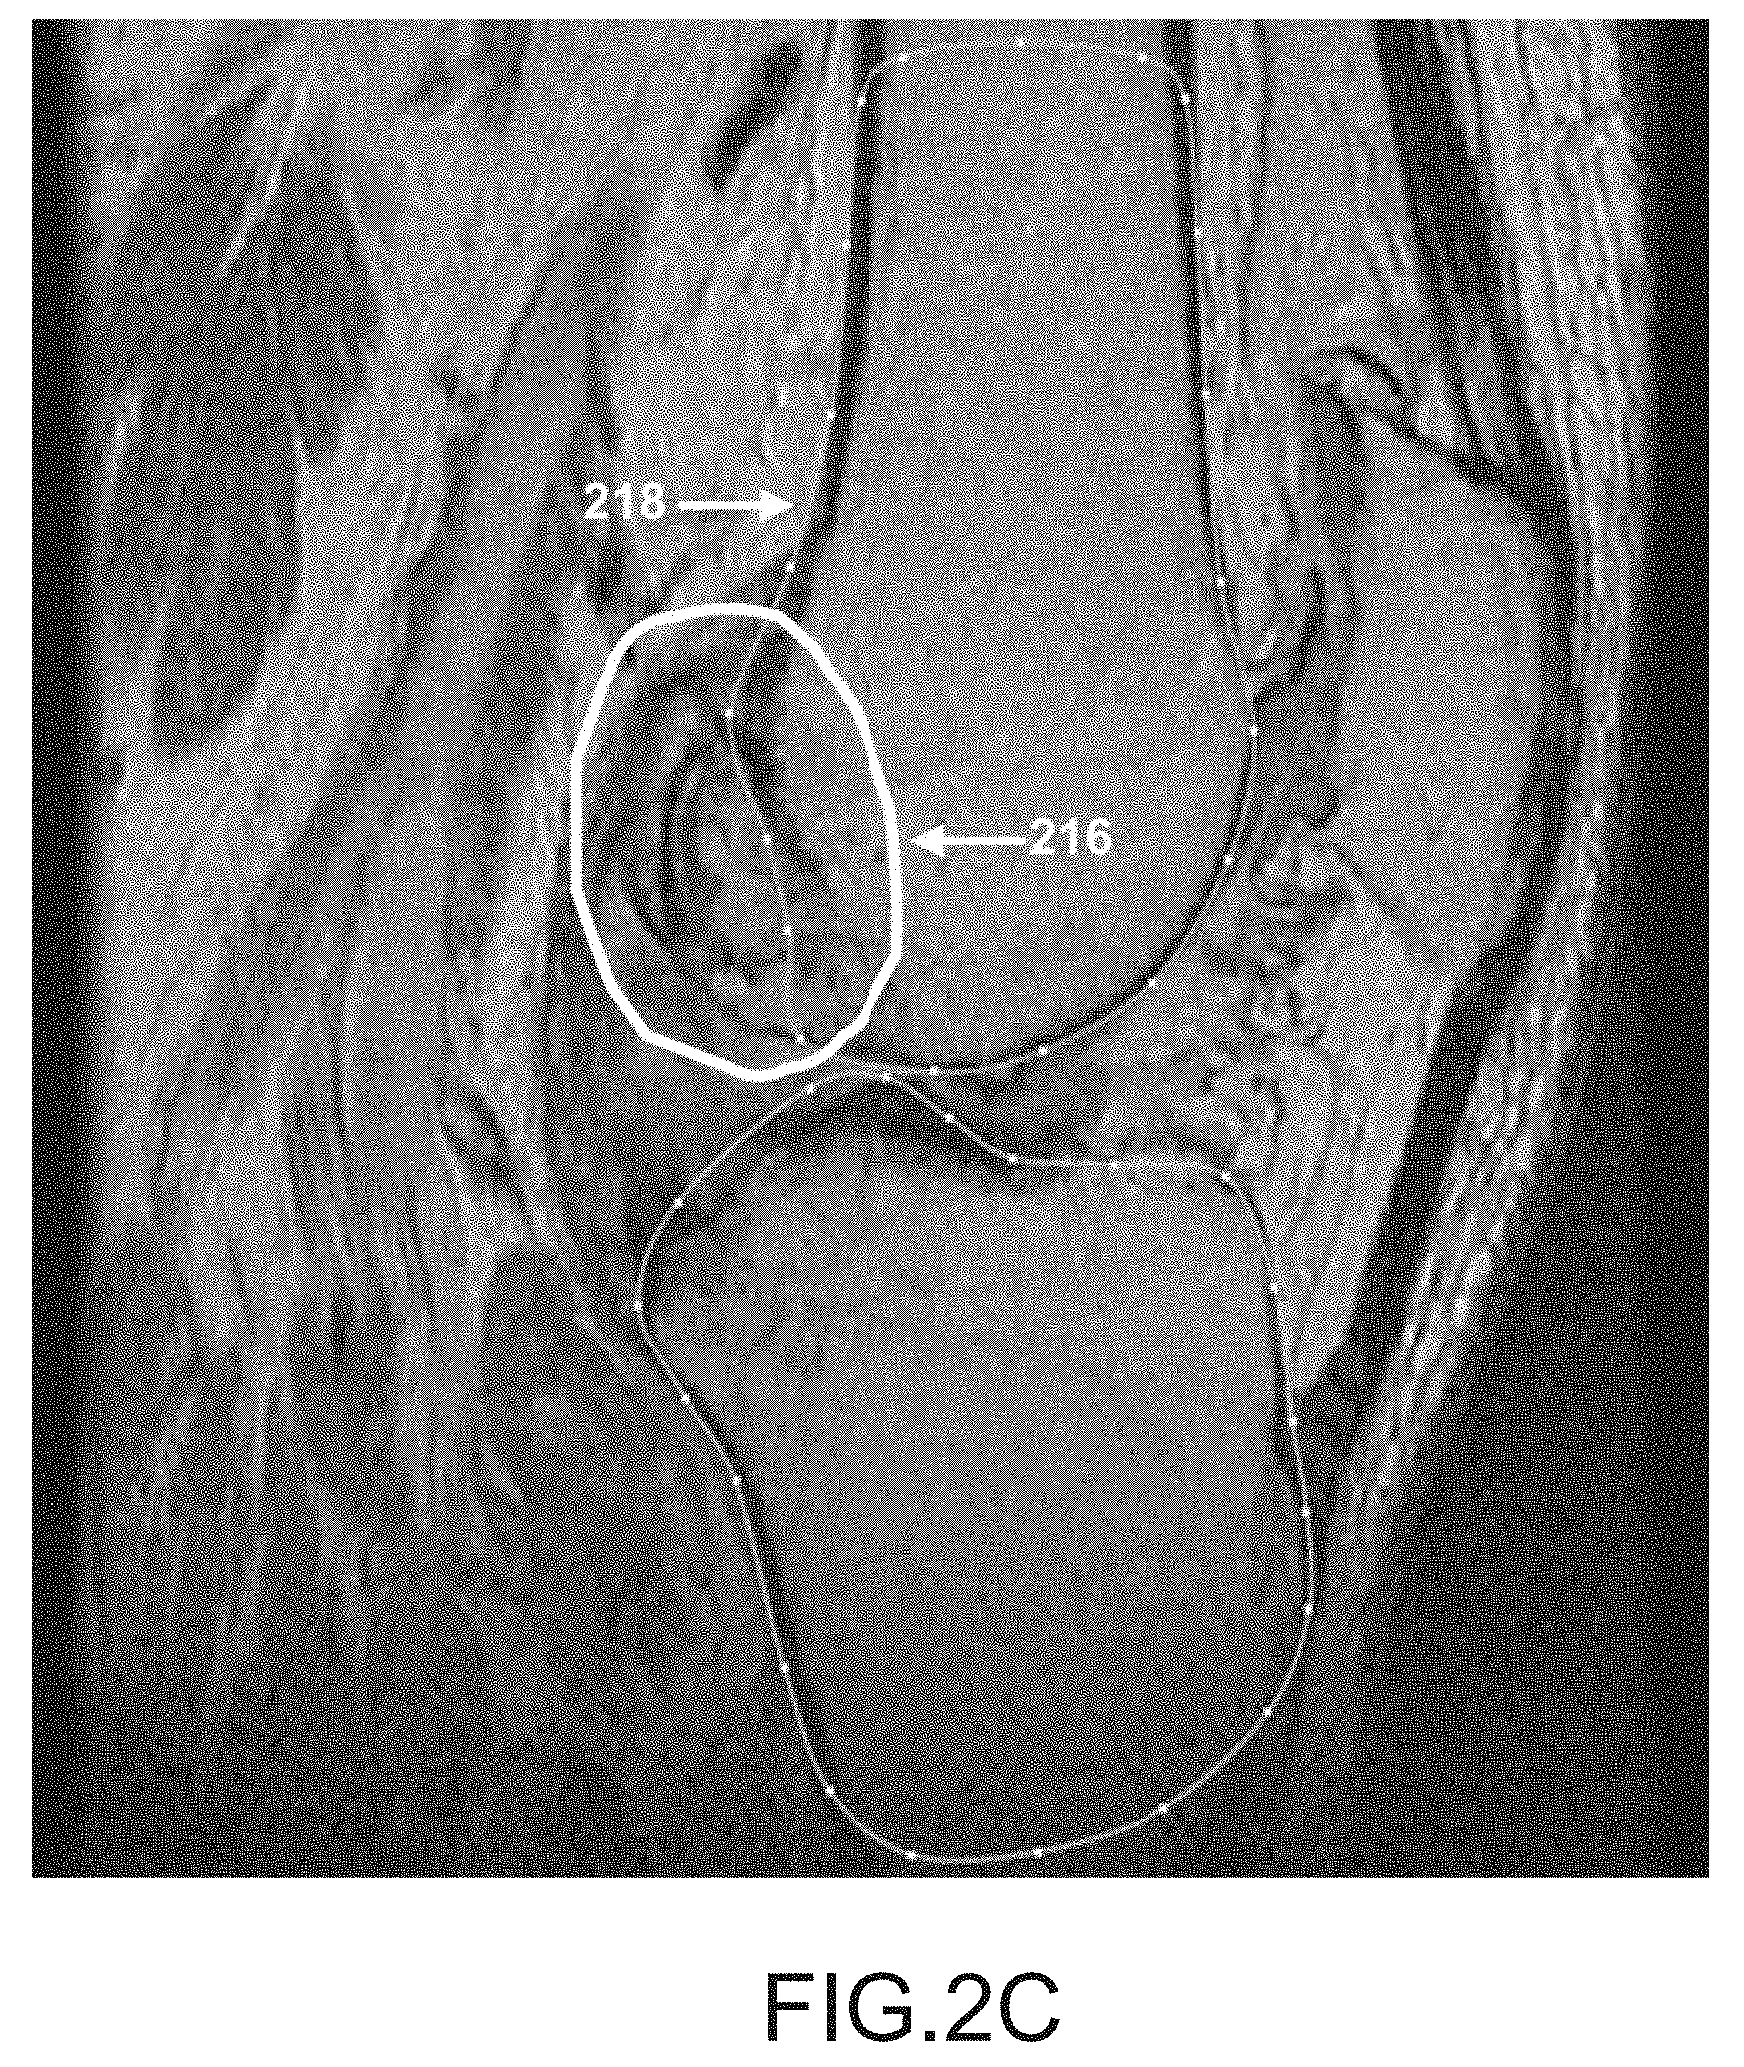

FIG. 2C is a sagittal plane image slice depicting a region of a femur that is approximately tangent to the image slice.

Typical MRI and CT scan data generally provide images where parts of a bone boundary of interest may be well defined while other parts of the bone boundary may be difficult to determine due to voxel volume averaging, the presence of osteophyte growth, the presence of tissue having similar image intensities in neighboring areas to the object to be segmented, amongst other things. Such poor definition of parts of the bone boundary in the images may cause traditional automated segmentation techniques to fail. For example, FIG. 2A depicts regions 212 within a slice where an object boundary may not be visible due to neighboring tissue having about the same intensity as the feature of interest. Depicted in FIG. 2B are regions 214 that may be extended into the slice from adjacent slices due to a high voxel aspect ratio. Depicted in FIG. 2C is a region 216 of the bone boundary 218 that may disappear or lose regularity when the bone boundary 218 is approximately tangent to the slice.